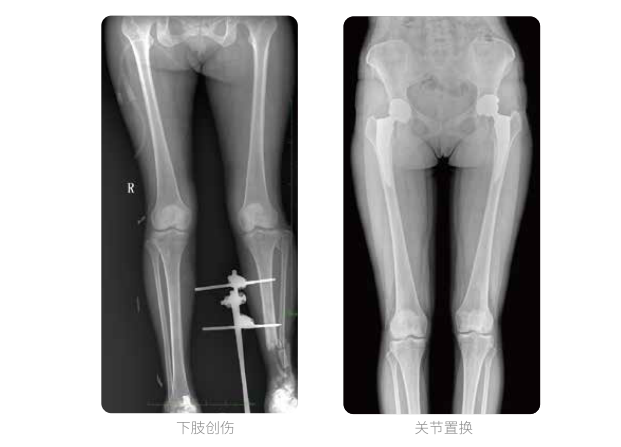

一次曝光 讓較長髓內(nèi)釘細(xì)節(jié)畢現(xiàn)

雙下肢臨床影像

髓內(nèi)釘手術(shù)是骨科、手足外科中常見的微創(chuàng)型手術(shù)方式,患者隨訪時(shí)需拍攝置入在股骨、肱骨處的較長髓內(nèi)釘。PLX8600視野拍攝,能夠出色解決醫(yī)生需多次攝影再拼接的痛點(diǎn)。一次成像雙下肢,即拍即得,高效率,無需拼接。工作站軟件自帶的測(cè)量功能方便醫(yī)生讀取雙下肢長度數(shù)據(jù),助力準(zhǔn)確診斷。

動(dòng)態(tài)DR所具備的全脊柱、全下肢全景成像技術(shù)檢查,能夠更加清晰的顯示患者病情變化情況,對(duì)骨科疾病患者的全脊柱、全下肢病變情況圖像展示更加具有完整性,對(duì)患者在自然狀態(tài)下的應(yīng)力情況展示較為全面,有助于骨科疾病患者臨床診斷效果的提升,對(duì)患者臨床治療方案的科學(xué)制定有著積極的作用。